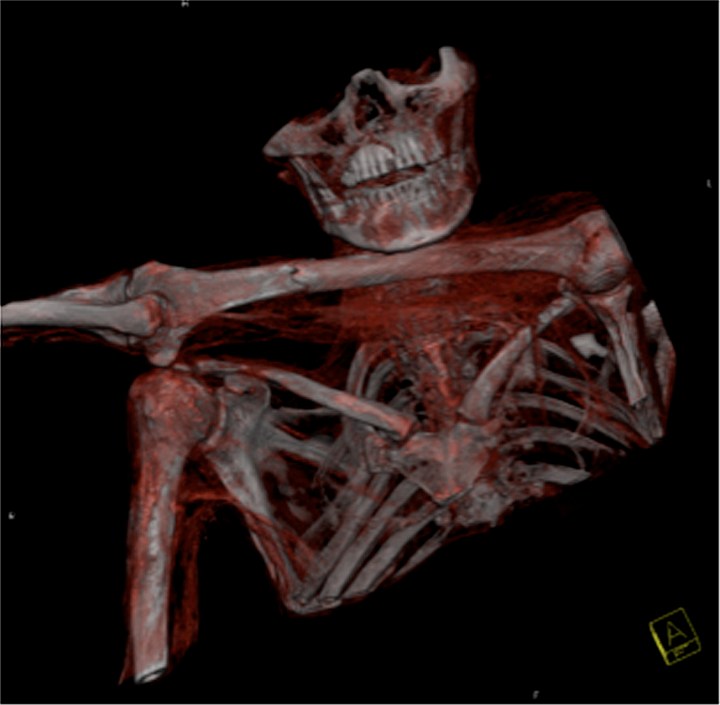

Gli studiosi dell’ospedale di Bolzano e del CNR sono riusciti a ottenere quella che loro stessi chiamano un’approssimazione del suo timbro vocale, al quale hanno affidato l’emissione di cinque semplici suoni: le vocali italiane. Qualcuno forse si aspettava di più ed è rimasto deluso da questi ‘vagiti’ senza senso. Si tratta però della miglior approssimazione possibile al momento: far parlare Ötzi, infatti, è un processo complicato. L’idea di provare a immaginare la sua voce è del foniatra dell’ospedale di Bolzano, Francesco Avanzini: «La mummia è sottoposta periodicamente a delle Tac, sulla base di queste immagini abbiamo ricavato il profilo del condotto vocale, cioè tutte le cavità che stanno al di sopra delle corde vocali e costituiscono un po’ la cassa armonica della voce». Impossibile non notare che le vocali di Ötzi hanno un marcato accento altoatesino: «Non siamo sicuri quale lingua parlasse Ötzi – spiega Avanzini – probabilmente il retico, vista la provenienza geografica. Diciamo che è un omaggio alla popolazione locale».

Un’operazione comunque non semplice perché la mummia ha una postura piuttosto ‘scomoda’: «Tutto quello che c’era è stato schiacciato dal braccio sinistro che ha spostato tutte le strutture del collo, compromettendo tutto il cavo sopraglottide – spiega Rolando Füstös, ex primario di Otorinolaringoiatria dell’ospedale regionale di Bolzano – ma abbiamo ‘rimesso virtualmente insieme i pezzi’». Questi risultati sono solo un primo passo. Un giorno, gli studiosi ne sono sicuri, lo sentiremo articolare anche parole di senso compiuto, ma servirà del tempo: «Certo può apparire sgradevole, non è proprio una voce – ammette Rolando Füstös, ex primario di Otorinolaringoiatria dell’ospedale regionale di Bolzano – ma è comunque verosimile e fatta su misure giuste, senza autopsia. Si tratta di un inizio promettente che ha generato molto entusiasmo. In futuro procederemo con ulteriori misurazioni per arrivare a una voce più vicina e quella reale».